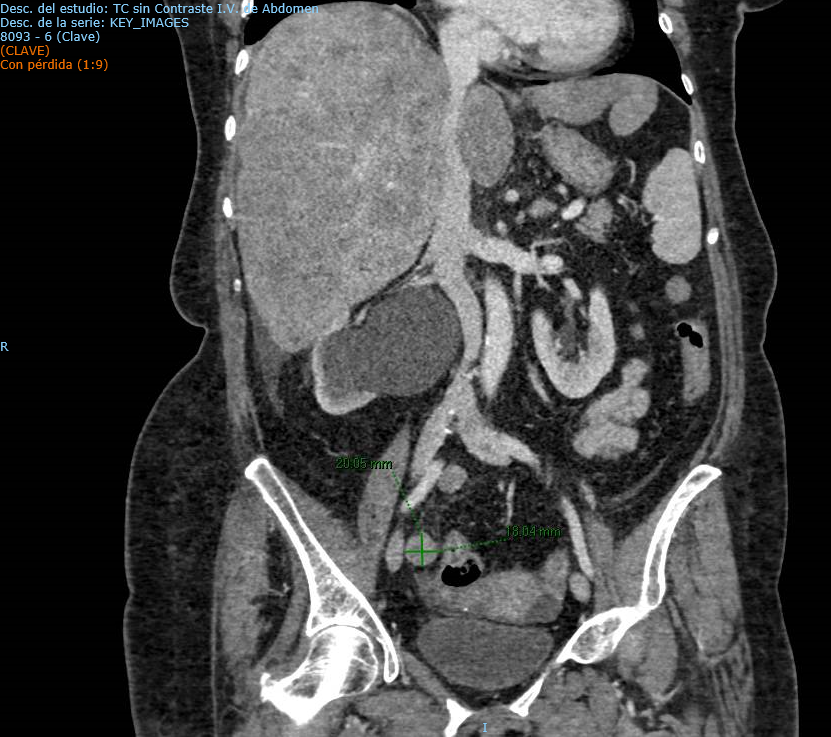

Se realiza una Tomografía Computarizada (TC) de abdomen y pelvis, objetivando una neoformación de aproximadamente 4 cm en uréter distal derecho que condiciona ureterohidronefrosis grado IV. Asocia adenopatías de probable naturaleza metastásica en territorio ilíaco derecho y en hilio hepático.